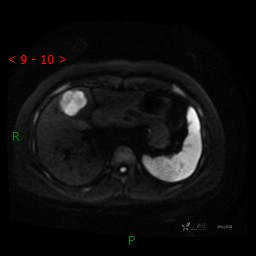

DWI